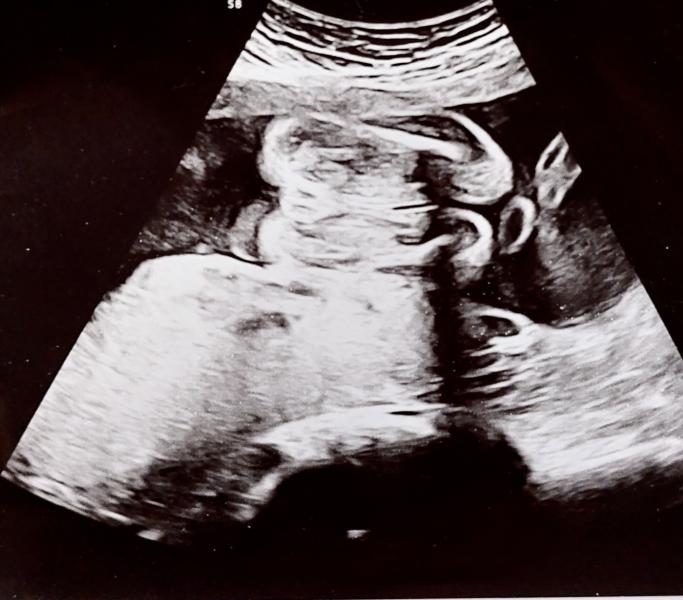

Вопрос ради просто интереса, первая моя беременность, на узи сказали что девочка, моя мама каким-то образом постоянно хочет увидеть там мальчика. Срок 23 недели, есть только такое фото узи

Изначально вообще не могла понять как малышка лежит на этом фото😅

На картинке слева это попка и кофейное зернышко по середине это вагина. А справа это ножки, может маме вашй ьам кажется что может быть пенис где то.